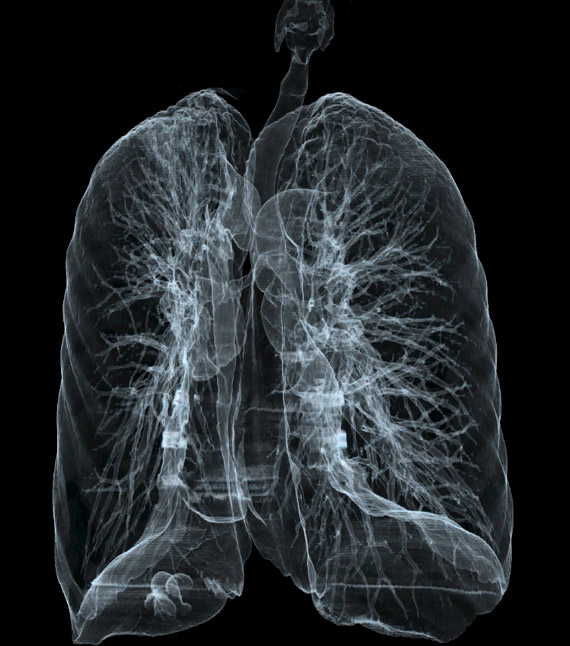

Introducerea tehnicii de achiziție spirală, care a permis achiziția continuă și rapidă a unui volum de date uriaș, cu posibilitatea de reconstrucție ulterioară în orice plan, nu doar cel transversal, precum și cu posibilitatea de reconstrucții tridimensionale spectaculoase. Inițial, achiziția se făcea doar în modul secvențial: după o rotație de 360 de grade a tubului, masa cu pacientul avansa în interiorulul aparatului cu grosimea unui slice (de obicei 10mm) și se făcea o noua achiziție. Acest mod este mai lent și nu permite reconstrucții în alt plan la fel de ușor ca achiziția spirală, la care tubul se învârte continuu, iar masa se mișca și ea în același timp. În prezent, achiziția secvențială se mai utilizează de rutină numai la examinarea cerebrală.

Creșterea vitezei de achiziție a imaginilor, în prezent putem obține imaginea statică a inimii (întreaga inima văzută într-o singură bătaie de inimă). Se obțin secvențe din ce în ce mai fine, slice-ri cu grosime de 0.5-1mm și rezoluții geometrice din ce în ce mai mari.

Algoritmii de reconstrucție sunt din ce în ce mai buni, putând reprezenta tot mai exact anatomia internă a corpului, cu iradiere din ce în ce mai mică. Reconstrucțiile tridimensionale devin mai exacte decât atlasele de anatomie și în felul acesta un extraordinar material didactic pentru studenți și rezidenți.

Evolutia calculatoarele permite in prezent prelucrari complexe ale imaginii achizitionate, pe console speciale, fara a mai fi nevoie de prezenta pacientului. Astfel, imaginile sursa sub forma unui volum impresionant de date ce acopera o anumita regiune a corpului pot fi prelucrate in multiple moduri: